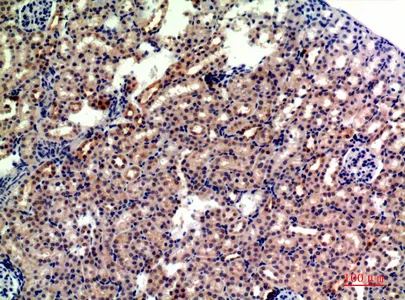

P-Selectin Rabbit Polyclonal Antibody

Cat: APRab16595

Size1:50μl Price1:$118

Size2:100μl Price2:$220

Size3:500μl Price3:$980

Size2:100μl Price2:$220

Size3:500μl Price3:$980